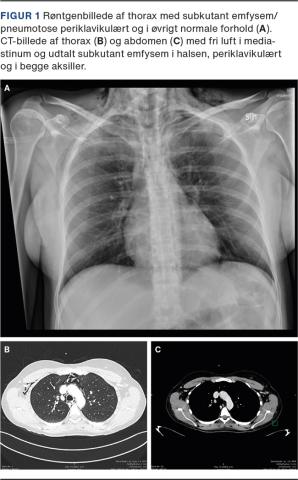

En 35-årig, sund og rask andengangsfødende (sectio antea) med ukompliceret graviditet blev indlagt på en fødegang pga. for tidlig bristning af fosterhinderne og veer ved gestationsuge 36 + 1 dag. Fødslen forløb ukompliceret indtil slutningen af pressefasen, hvor patienten begyndte at klage over trykkende smerter i brystet og hæs stemme. Umiddelbart efter fødslen bemærkedes der ligeledes nasal tale og tiltagende hævelse omkring højre orbita samt breddeøget halsregion og knitrende lyd i huden ved palpation. Den vagthavende læge blev tilkaldt, da der var fortsat trykkende brystsmerter. Early warning score var 0. Patienten fik ilt på næsekateter, og på mistanke om pneumothorax blev der foretaget akut røntgenoptagelse af thorax på stuen. Optagelsen viste normale forhold fraset et subkutant emfysem/pneumotose periklavikulært (Figur 1A). Der blev foretaget CT af thorax et par timer efter fødslen for at få afklaring og status på tilstanden, da hun fortsat havde nasal tale, men i øvrigt var upåvirket. CT’en viste fri luft i mediastinum og udtalt subkutant emfysem i halsregionen, periklavikulært og i begge aksiller (Figur 1B + C).